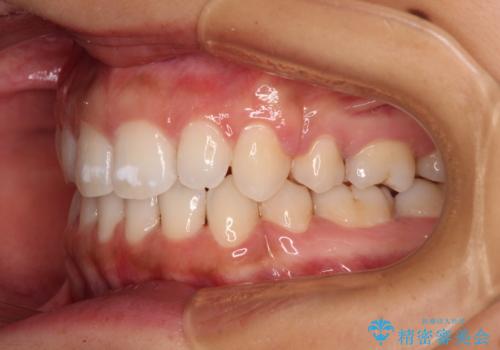

- 出っ歯で唇が閉じにくいとのことで来院された患者様です。

顎先に力を入れないと唇が閉じきれない口元であったので、上下左右の第一小臼歯4本を抜歯して、ワイヤー装置にて矯正治療を行うこととしました。

2年から2年半の治療期間を想定しており、予定通りの期間で無事に終了することができました。

唇や顎先に力を入れないなくてもスムーズに唇を閉じることができるようになりました。